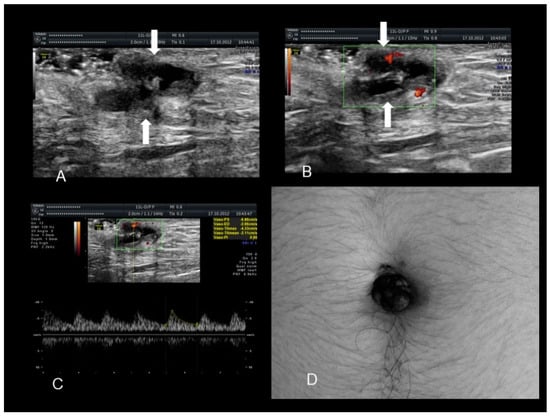

2.4. Rectus Abdominis Endometriosis

Endometriosis of the rectus muscle is an extremely rare localization of extra-pelvic endometriosis [19]. Ultrasonography usually demonstrates a heterogeneous hypoechogenic formation with indistinct edges [20] (Figure 6, Figure 7 and Figure 8). To help in the diagnosis, if the patient moves her legs alternatively during the examination the operator can easily visualize the muscular layers.

Figure 6. The ultrasonographic appearance of a rectus abdominis endometriotic nodule (see white arrows) (AD) in a woman with previous cesarean section and hysterectomy. The last picture (D) is taken during the needle biopsy.